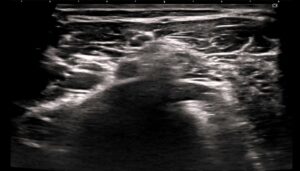

触覚異常の分布からC7神経根領域と推察。

エコーガイド下でC7神経根周囲に鍼治療を行ったところ、翌日には痛みが完全に消失。その後も再発はありませんでした。